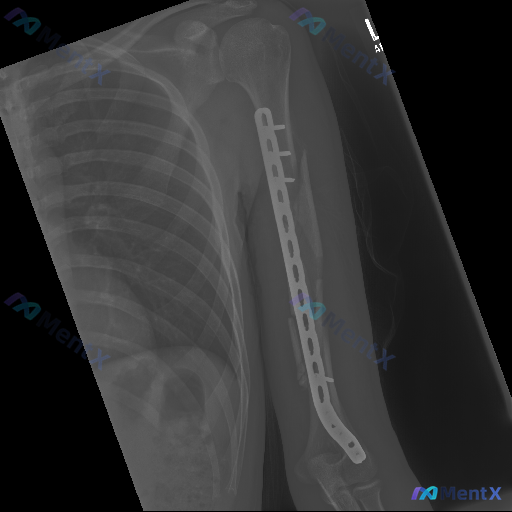

整理到一份骨科术后复查的影像病例资料,大家一起看看: 基本情况:左侧肱骨干骨折术后复查 影像表现(左侧肱骨正位X光): - 肱骨干可见长钢板内固定,多枚螺钉固定; - 肱骨干可见斜形及多段骨折线,断端明显骨质吸收、边缘硬化; - 部分螺钉周围可见透亮区; - 肱骨干中下段内侧可见一枚游离皮质骨碎片;...